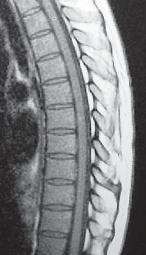

МРТ № 2

На МРТ № 2 — грудной отдел в состоянии «норма»

Грудной отдел должен иметь нормальную степень кифоза (угол кифоза по Stagnara формируется линией, параллельной замыкательным пластинкам ТIII и ТXI= 25°). Позвоночный канал на грудном уровне имеет округлую форму, что делает эпидуральное пространство узким почти по всей окружности дурального мешка (0,2–0,4 см), а на участке между TVI и ТIX он наиболее узок. Сагиттальный размер: ТIХI = 13–14 мм, ТXII = 15 мм. Поперечный диаметр: > 20–21 мм.

Высота межпозвонковых дисков: самая меньшая на уровне ТI, на уровне ТVIХI приблизительно 4–5 мм, наибольшая на уровне ТХIХII.